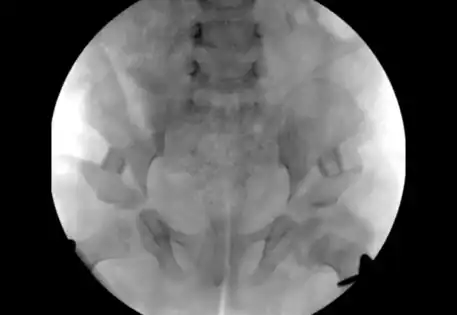

Hip dysplasia can manifest in various syndromes, including Prader-Willi syndrome, arthrogryposis, caudal regression syndrome, and Kabuki syndrome. Syndromic hip dysplasia cases in Dubai often involve more pronounced anatomical distortions, posing greater challenges in treatment and higher recurrence risks. Dr. Qureshi, a child orthopaedic doctor in Dubai, is experienced in addressing these complex cases, providing specialised care and management for each unique condition.

Dr. Qureshi has successfully managed numerous cases of syndromic hip dysplasia, employing investigations such as arthrography and CT imaging to assess reconstruction feasibility and plan surgical interventions. The treatment strategy is customarily crafted as a tailored combination of different techniques to address distinct components and contributory factors contributing to the dislocation.